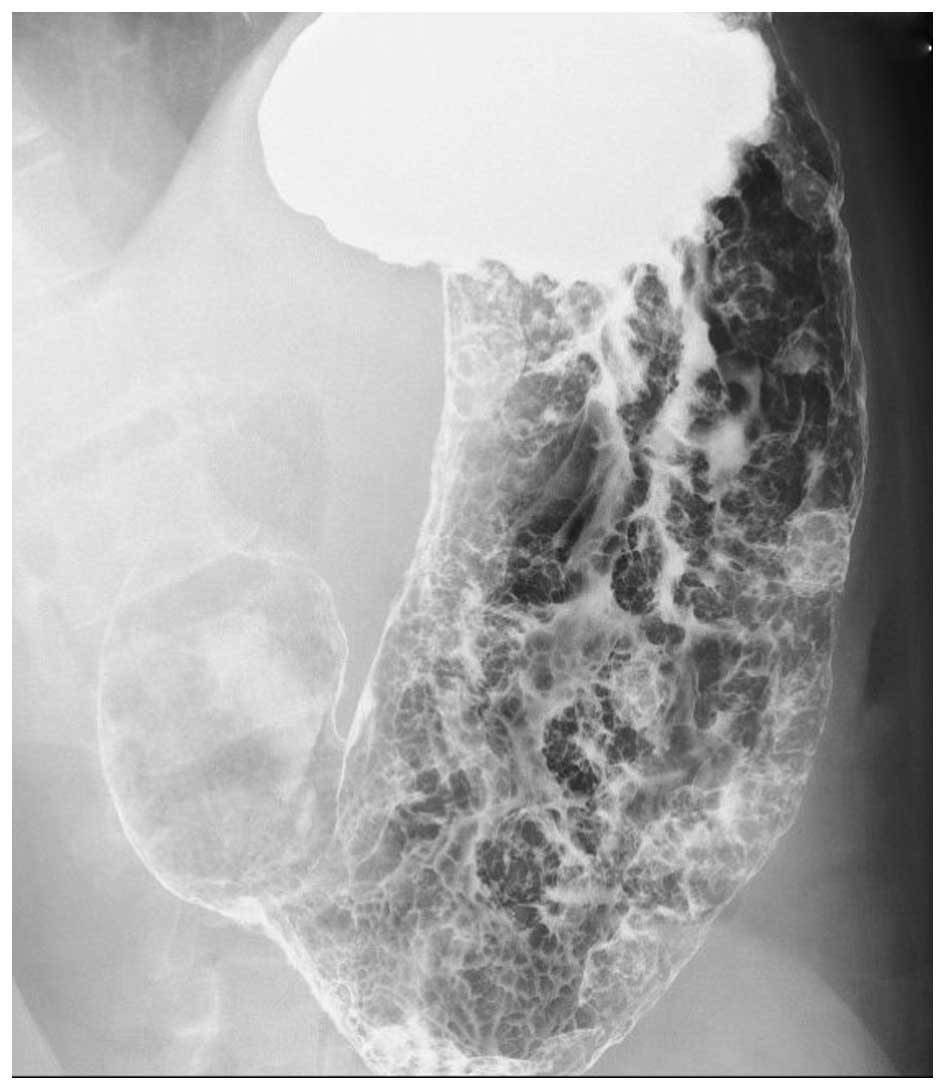

A 24-year-old man with an unremarkable medical history was referred to Onomichi General Hospital (Hiroshima, Japan) as a result of melena and anemia in 2004. An upper gastrointestinal endoscopy in 2004 revealed multiple edematous polyps around the fundus of the stomach (Fig. 1). Histological examination revealed a hyperplastic and disorganized foveolar epithelium, and an edematous lamina propria with infiltration of inflammatory cells, and the histological diagnosis was hyperplastic polyps. The patient began taking a proton-pump inhibitor and iron supplements, and he underwent an upper gastrointestinal endoscopy annually. The polyps appeared around the fundus in 2004 and had gradually progressed to the entire stomach in 2014 (Fig. 2). The number and size of the polyps had also increased. Endoscopic mucosal resection was performed frequently due to bleeding from the polyps. It was difficult to control the progressing anemia by non-surgical treatment, and, in 2014, histological examination revealed for the first time that the benign polyps were adenocarcinoma. Surgical treatment was therefore performed. At the time of surgery, the patient was 171 cm tall and weighed 62.5 kg. No skin lesions or loss of hair, which is characteristic of Cronkhite-Canada syndrome, was exhibited. Laboratory data demonstrated mild anemia (hemoglobin, 9.6 g/dl), but neither hypoproteinemia nor elevation of tumor markers, including carcinoembryonic antigen and carbohydrate antigen 19–9 was observed. With respect to the patient's family history, the patient's mother had succumbed to colon cancer in her 50s and his cousin had succumbed to an unknown primary cancer in his 30s. Colonoscopy revealed no specific findings. Enhanced computed tomography revealed that the stomach wall was edematous with enhanced thickening from multiple polyps (Fig. 3). An upper gastrointestinal series revealed that multiple polypoid lesions were limited to the entire stomach and were not present in the small intestine (Fig. 4). The patient underwent laparoscopy-assisted total gastrectomy with Roux-en-Y esophagojejunostomy. The resected specimen revealed numerous diffuse polyps throughout the entire stomach (Fig. 5). Microscopic findings revealed a hyperplastic and disorganized foveolar epithelium with an atypical nuclear shape. Enlargement of the nucleolus was also observed, and the patient was diagnosed with well-differentiated adenocarcinoma. A total of three lesions of early gastric cancer, and no lymph node metastasis were detected. Immunohistochemical staining revealed that the specimen was positive for p53 and carcinoembryonic antigen and exhibited a high index of mindbomb E3 ubiquitin protein ligase 1 (Fig. 6). The postoperative course was uneventful, hemoglobin level returned to the normal range, and the patient experienced no recurrence over a 1 year follow-up.

Figure 4.

Upper gastrointestinal series. An upper gastrointestinal series demonstrated that multiple polypoid lesions were widespread throughout the entire stomach.